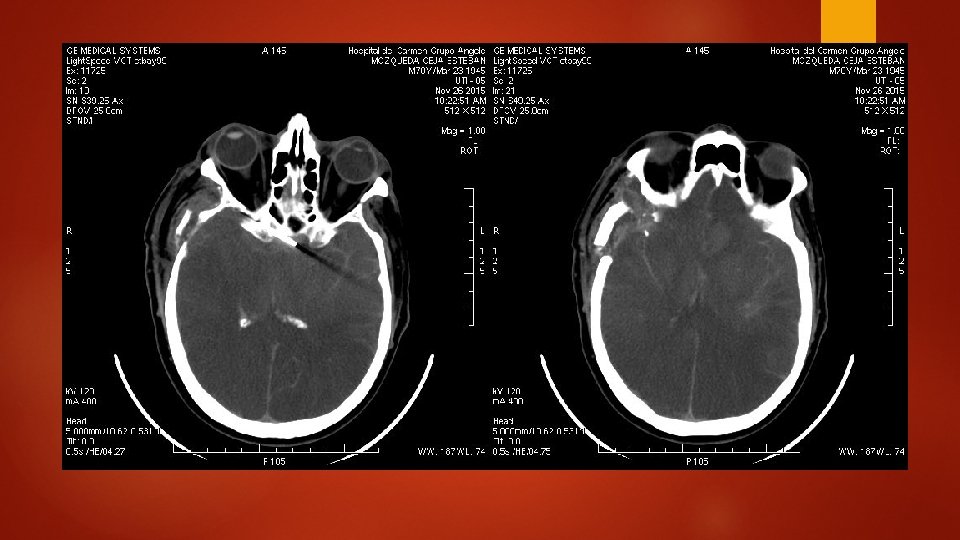

CT post-Clipaje (8 días después)

Interpretación radiológica Cambios postquirúrgicos con presencia de clip y craneostomía TAC de control sin evidencia de sangrado, con adecuada diferenciación entre sustancia blanca y gris.

INTERPRETACIÓN RADIOLÓGICA EDEMA CEREBRAL IMPORTANTE PÉRDIDA DE LA ARQUITECTURA CEREBRAL TOTAL PÉRDIDA DE RELACIÓN ENTRE SUSTANCIA BLANCA Y SUSTANCIA GRIS AUMENTO DE LA HEMORRAGIA SUBARACNOIDEA